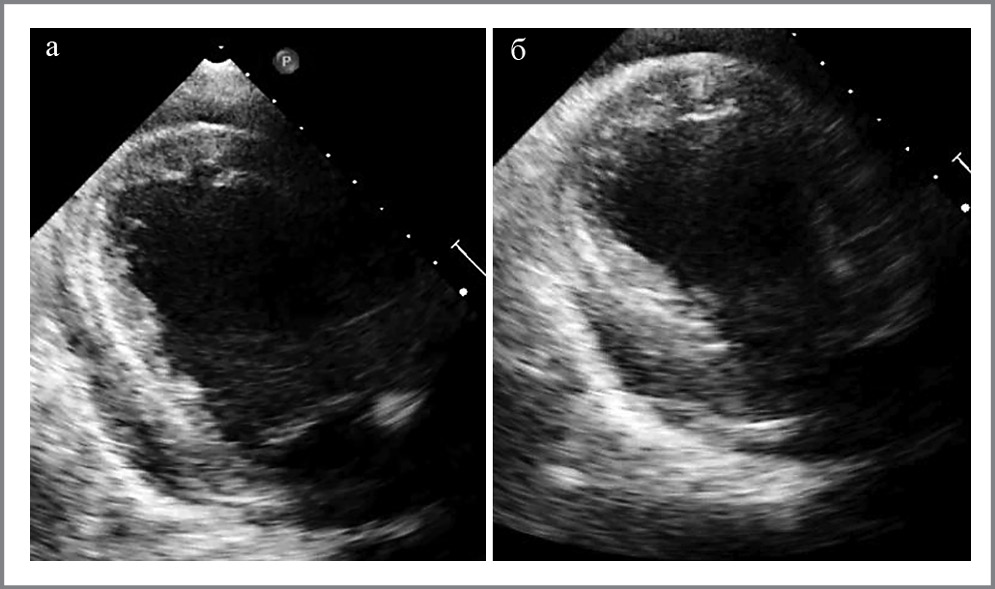

Рис. 2. ЭхоКГ при поступлении. Высокий дефект внутрижелудочковой перегородки (указан стрелкой) с определением соотношения легочного и системного кровотока.

Fig. 2. Echocardiography (EchoCG) on admission. High intraventricular septum defect (indicated by the arrow) with determining the ratio of pulmonary and systemic blood flow.

По данным эхокардиографии (ЭхоКГ): АС тяжелой степени – максимальная скорость 4 м/с, средний систолический градиент на АК 40 мм рт. ст., площадь раскрытия (планиметрически) 0,6 см2. Кальциноз АК 3-й степени. Аортальная недостаточность 2-й степени. Перимембранозный ДМЖП (диаметр около 7,5 мм) с двунаправленным сбросом крови, максимальный градиент давления между правым желудочком и ЛЖ – 50 мм рт. ст., соотношение легочного и системного кровотока QP/QS=0,8 (рис. 3). Высокая ЛГ (систолическое давление в ЛА – 103 мм рт. ст.), давление заклинивания ЛА – 19 мм рт. ст. Расширение обоих предсердий и правого желудочка (переднезадний размер 4,2 см), TAPSE – 0,9 см. Выраженная концентрическая гипертрофия миокарда ЛЖ (толщина МЖП – 1,5 см). Сократимость ЛЖ относительно удовлетворительная, фракция выброса – 57% (по Симпсону), конечно-диастолический размер ЛЖ – 4,4 см, ударный объем ЛЖ снижен (27 мл). В полости перикарда – до 120 мл жидкости. Признаки высокого центрального венозного давления.